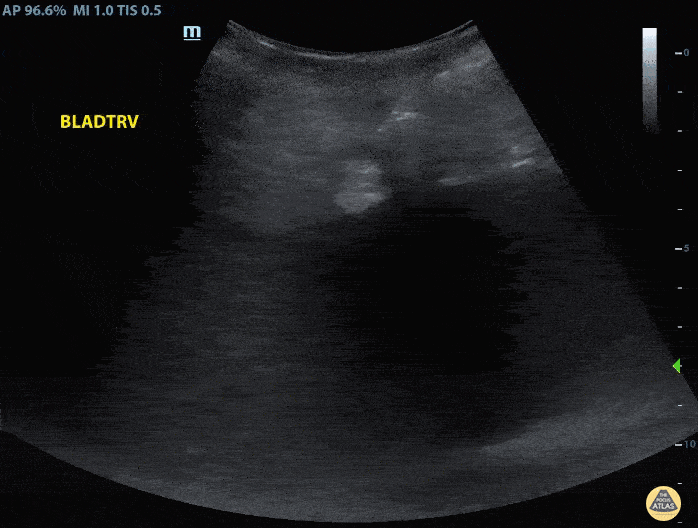

60s M presented to the ED sent in by PMD for evaluation of elevated BUN and Creatinine. POCUS performed with transverse view of the urinary bladder demonstrating discrete cystic structure on anatomic right with second circular, hyperechoic structure visualized. Structures are consistent with penile prosthesis fluid reservoir abutting the right anterior bladder. Findings confirmed on chart review of previous urinary bladder imaging. Hydraulic inflatable prostheses consist of two or three piece types. The three piece types (as pictured) consist of a pair of cylinders placed in each corpus cavernosum, a pump placed in the scrotum, and a reservoir placed adjacent to the bladder (1). Yahyavi-Firouz-Abadi N, Menias C, Bhalla S, Siegel C, Gayer G, Katz D. Imaging of Cosmetic Plastic Procedures and Implants in the Body and Their Potential Complications. AJR Am J Roentgenol. 2015;204(4):707-15. doi:10.2214/AJR.14.13516 - Pubmed Contributors: Joshua Taubman MD, Resident Physician - University at Buffalo Emergency Medicine, @UBEMSono